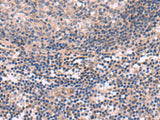

KCNT1 Polyclonal Antibody

Applications IHC

IHC 1:30-1:150